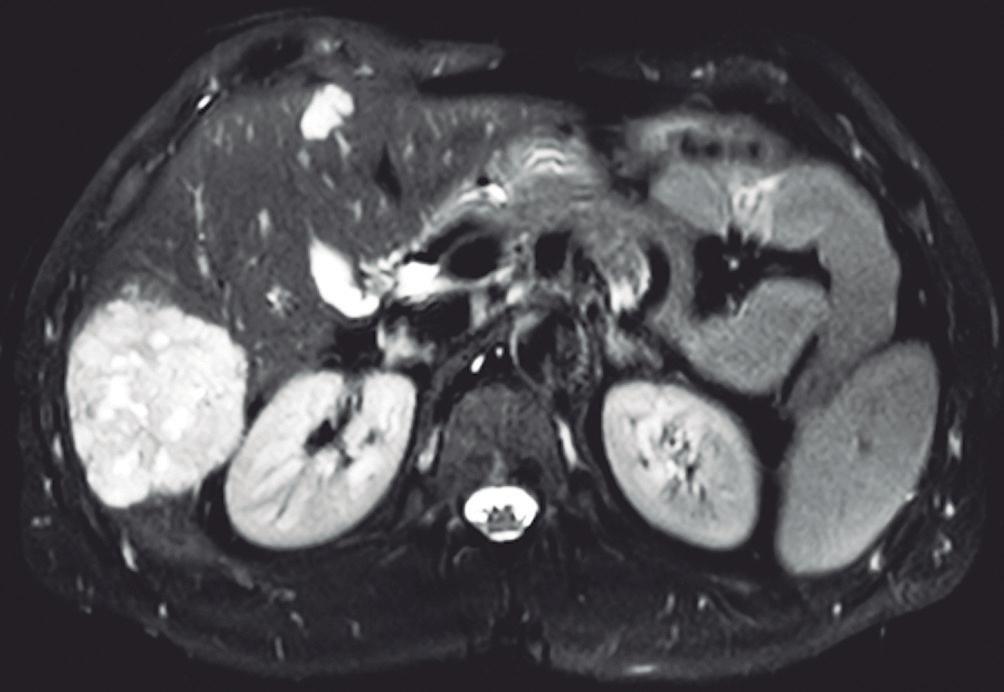

En la RM los hemangiomas son lesiones con señal hipointensa en T1 e hiperintensa muy marcada en T2. Esta última característica los diferencia de otras lesiones benignas o malignas, con excepción de los quistes, que presentan señal más elevada debido a su contenido acuoso.1 El patrón de realce poscontraste es igual al que muestra la TC. (Figura 2) En la secuencia de difusión no presentan un patrón restrictivo, si bien pueden exhibir una señal brillante en valores b altos (parámetro que pondera la difusión); esto se debe al efecto brillo T2 y no a la restricción verdadera, por lo que el mapa del coeficiente de difusión aparente (ADC, por sus siglas en in-

A: T1 post contraste en fase venosa portal; B, y fase de equilibrio; C: Muestran lesiones en segmentos IV y VI con una señal marcadamente hiperintensa en la secuencia T2 y

Lesiones benignas localizadas en el hígado desde la mirada de las imágenes Mariano Volpacchio Figura 1. Hemangioma en tomografía computada. Imágenes axiales de la TC sin contraste Figura 2. Hemangioma en la RM. Imágenes axiales de la RM en secuencia T2 con supresión grasa con el refuerzo similar a las estructuras vasculares de aspecto globular y progresivo en sucesivas fases. Nótese la heterogeneidad del hemangioma de mayor tamaño en segmento VI. A B C